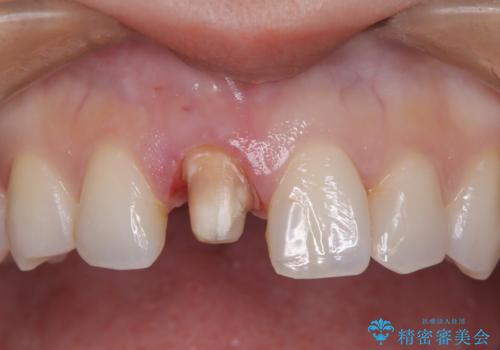

- 前歯のガタつき、変色を主訴に来院された患者様です。術前診査のCT撮影にて、変色した前歯の根の先に病巣があることが判明しました。そこで、マウスピースによる矯正治療と、前歯の根管治療、かぶせ物のやり直し治療を並行して行いました。